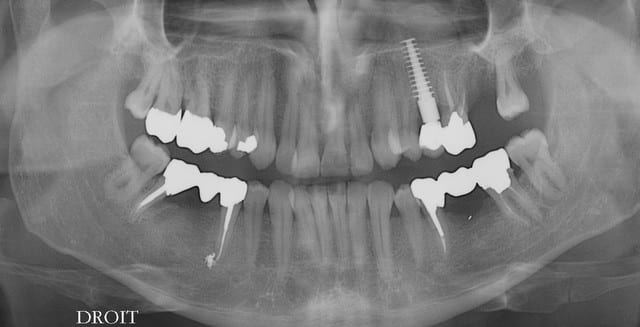

mon petit pâté de ce matin: lift droit et gauche et implantations

très mauvaise gestion de mon stock d'implants.....javais plus que du 11.5 pour placer dans la zone liftée à gauche! m'enfin çà tiendra quand même.

à droite discret Summers.